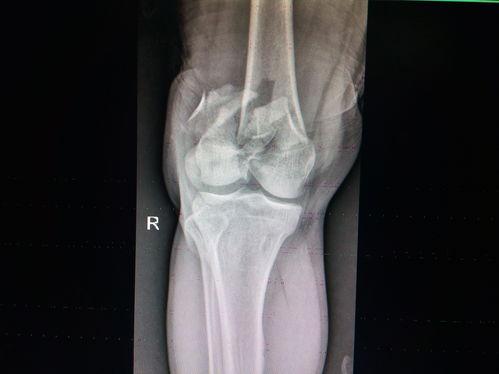

手术过程中,医生会根据你的病情选择合适的手术方式。如果是关节镜手术,他们会将镜子插入你的膝盖,然后进行操作。如果是开放式手术,医生会在你的膝盖处切开一个切口,然后进行修复。

比如,有一位名叫李女士的患者,因为膝盖疼痛严重影响生活,最终选择了关节镜手术。手术结束后,她按照医生的指导进行康复训练,现在已经可以正常行走,生活也恢复了往日的精彩。

还有一位名叫张先生的患者,因为膝盖骨折,进行了开放式手术。虽然恢复过程比较痛苦,但他依然坚持下来,最终成功康复。